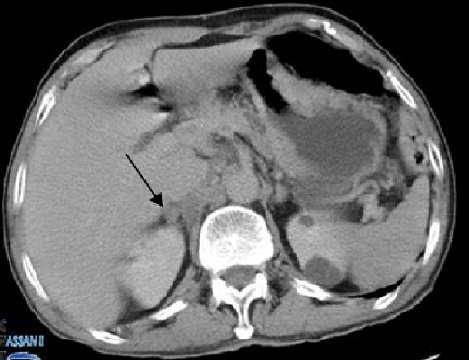

Monsieur F M âgé de 70 ans, originaire du Maroc, sans antécédents pathologiques notables, consultait pour des nodules angiomateux de la face, des extrémités et de la muqueuse buccale avec un oedème de la main gauche (Figure 1) évoluant dans un contexte de conservation de l’état général. La biopsie cutanée avec étude immunohistochimique était en faveur d'une maladie de kaposi. La sérologie HIV était négative. La fibroscopie oeso-gastro-duodénale avait montré la présence de 4 lésions mesurant chacune 10mm au niveau gastrique avec une biopsie en faveur d'une MK. La tomodensitométrie thoraco-abdominopelvienne avait objectivé un nodule surrénalien droit de 26mm (Figure 2). Le patient a été classé comme forme méditerranéenne de la MK avec atteinte multiviscérale, mis sous polychimiothérapie à base d'Adriablastine, Bléomycine et Vinblastine. Après 6 cures on a eu une amélioration clinique, endoscopique et une stabilité radiologique sans l'apparition de nouvelles lésions avec un recul de 2 ans.

Figure 2.

Nodule tissulaire surrénalien droit de 2,6cm